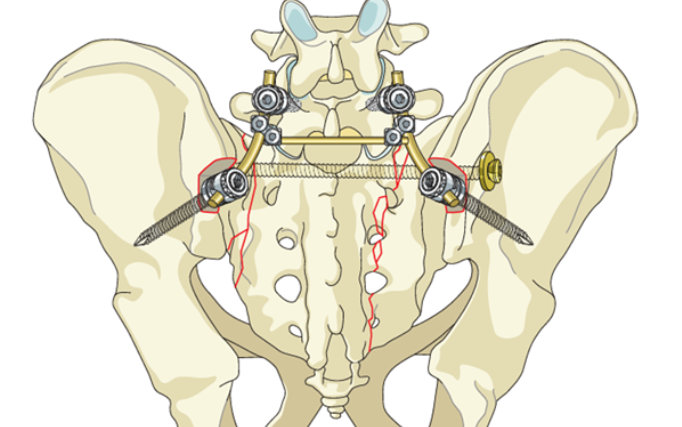

Süňk we bogun inçekeseli.

Süňk skeletinden geçýän keseller

Aritmiýalaryň hirurgiki bejergi usullary